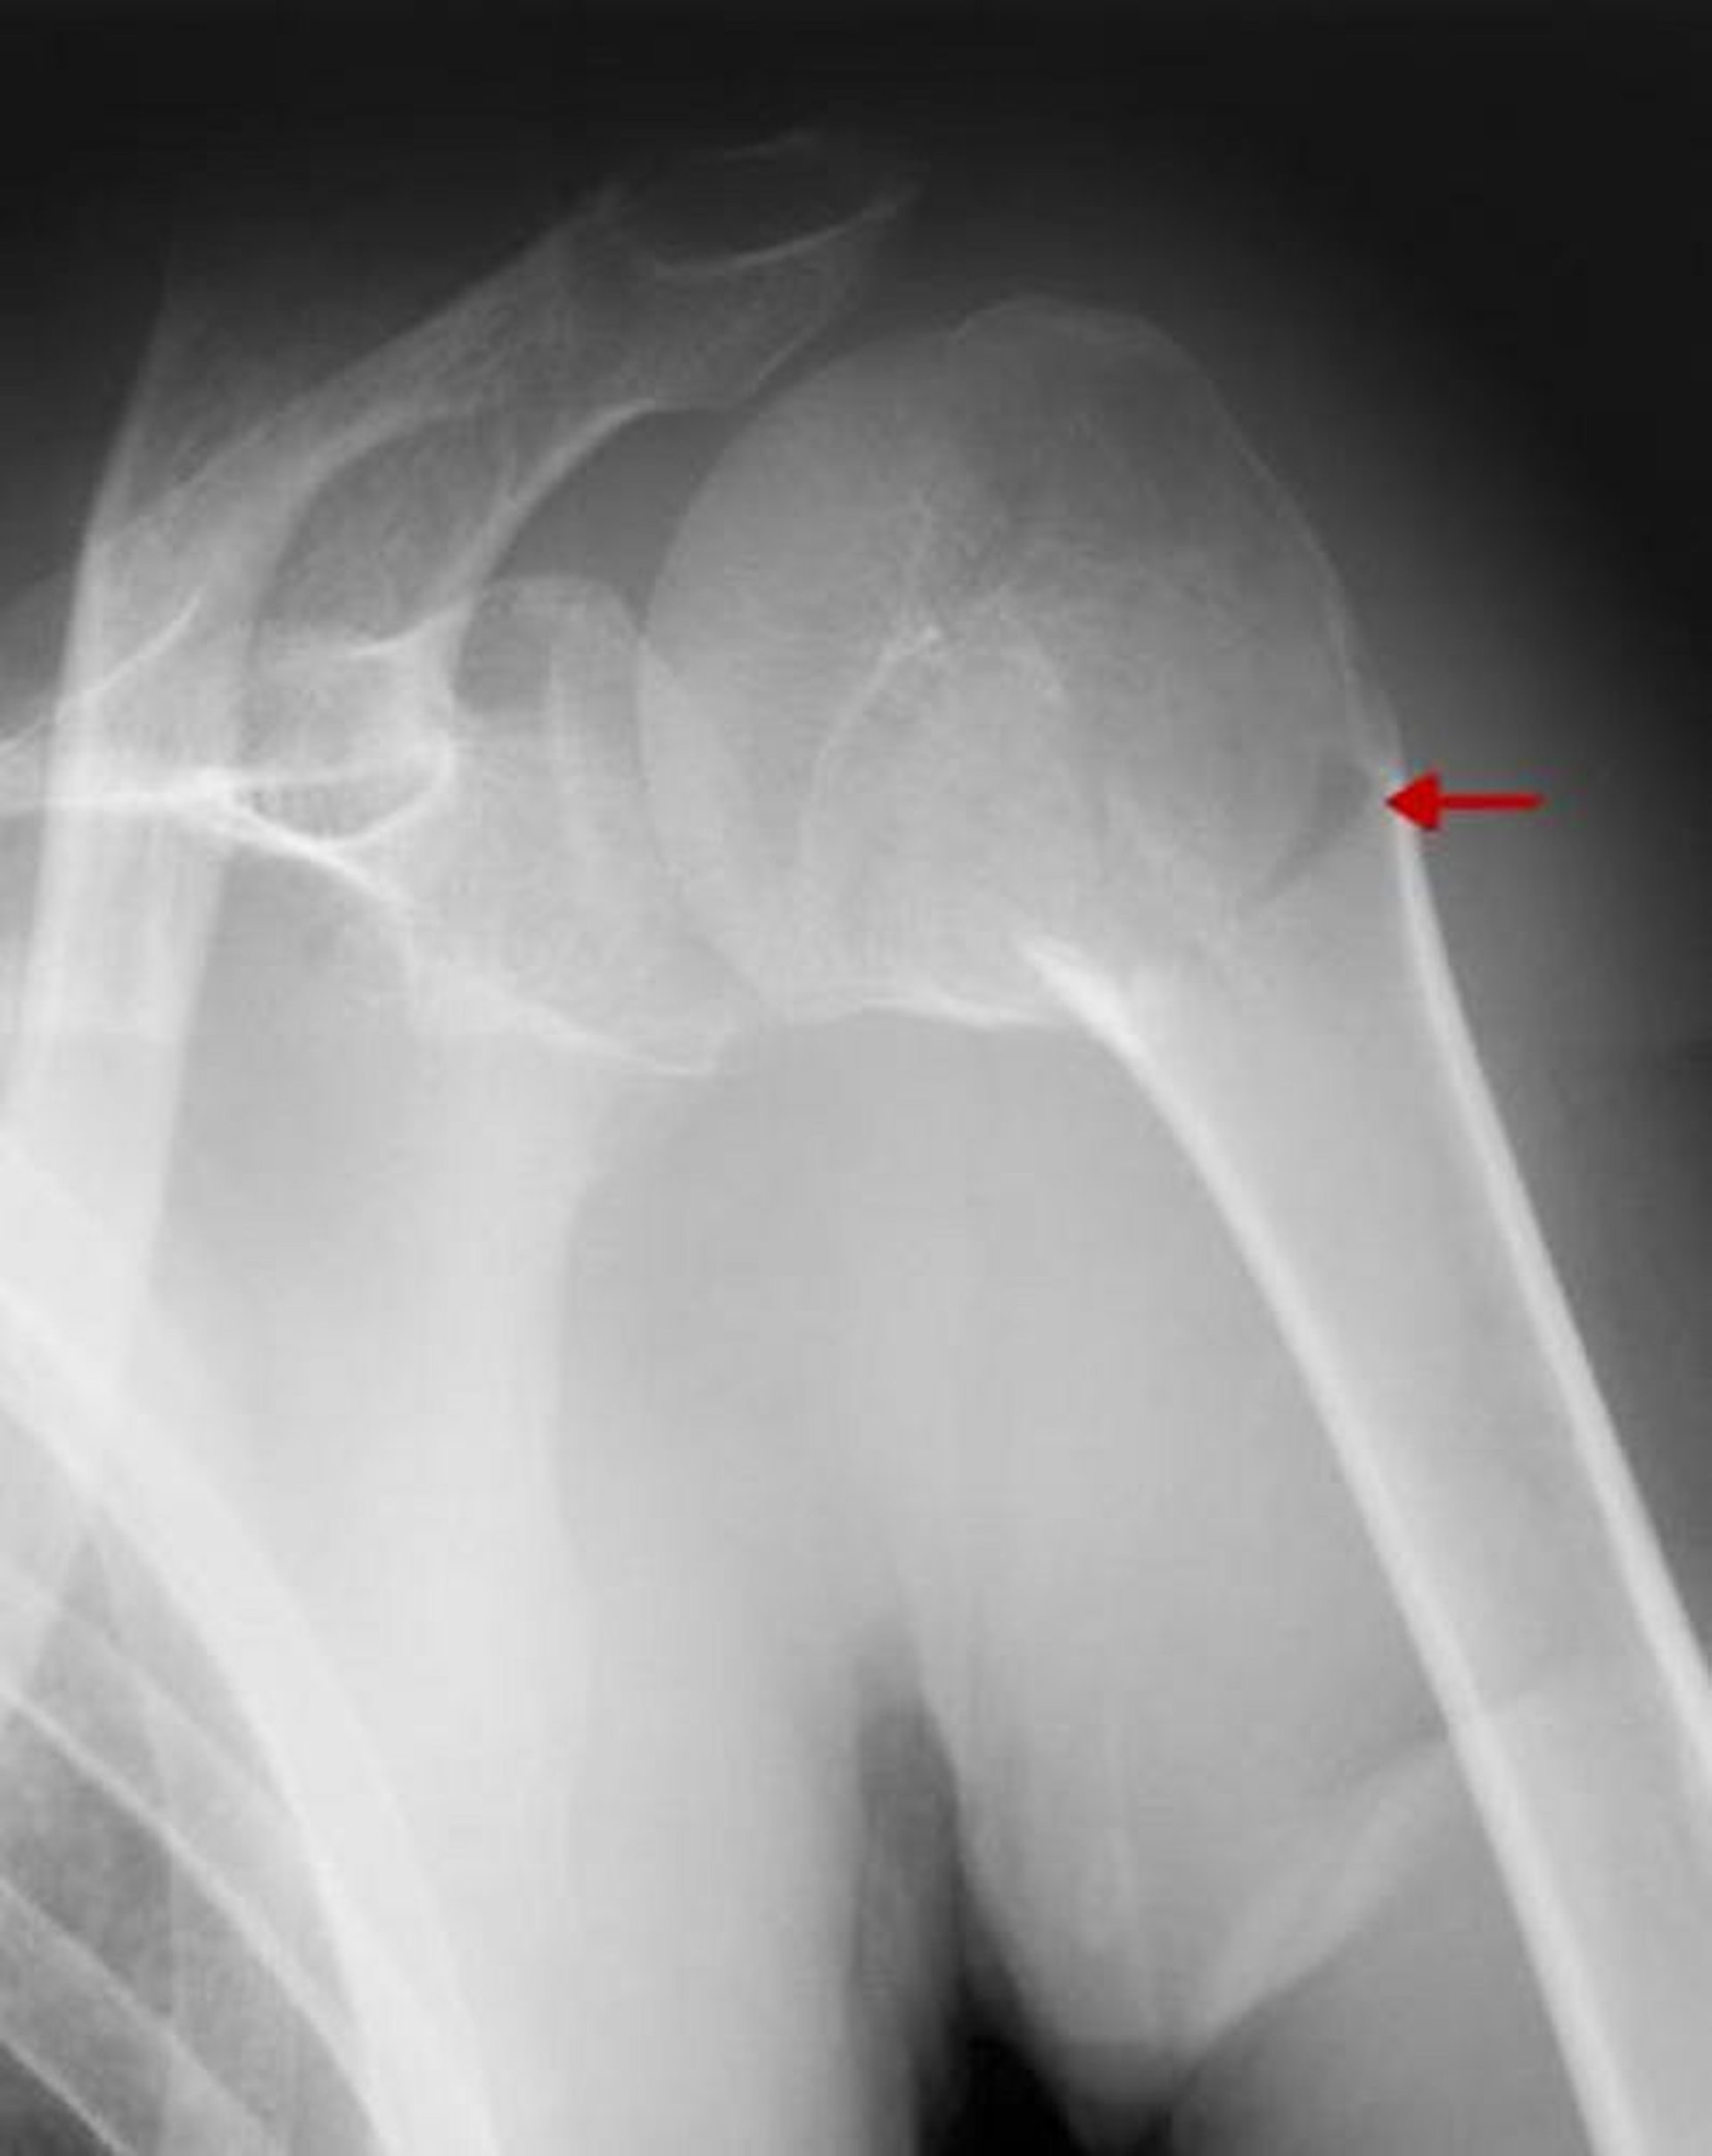

Frattura prossimale dell'omero

Questa frattura coinvolge il collo chirurgico. Poiché non vi è uno spostamento significativo o un'angolazione > 45°, si tratta di una frattura a un frammento.